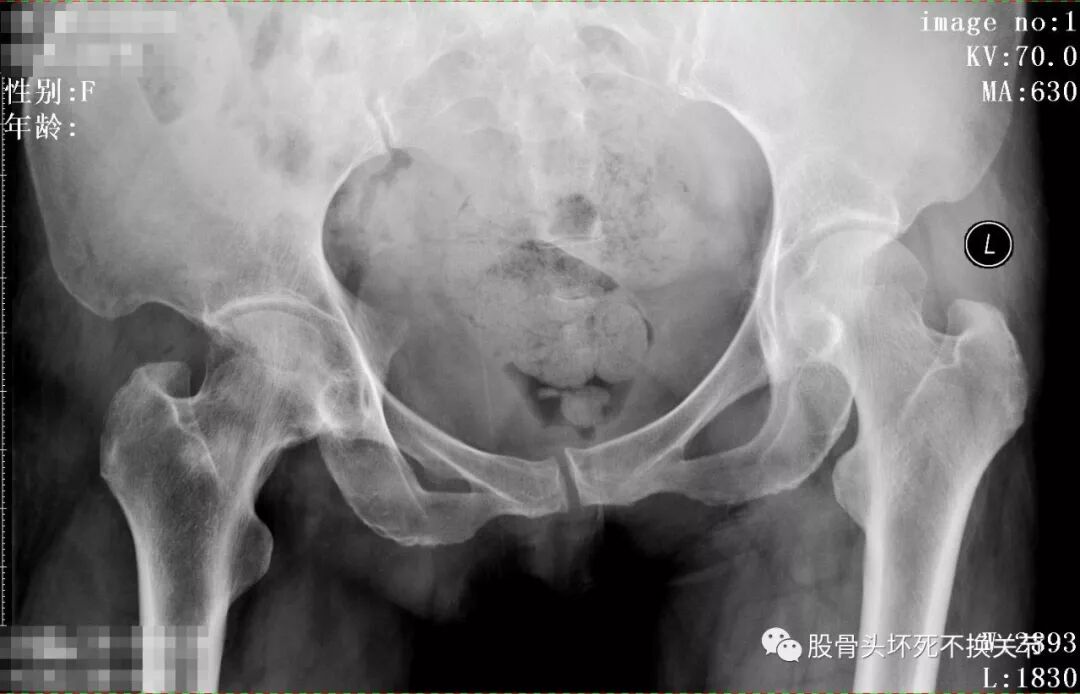

一般情况:女,42岁,右髋关节疼痛、穿鞋袜困难4年,曾被诊断为滑膜炎,经药物熏洗、口服药(各种止痛药、活血化瘀药)及各种理疗治疗4年均不凑效,前来我科诊治,以滑膜炎待查收入院。

从这些歪斜的X线片子可以看到,双髋关节并无特殊表现,双侧骶髂关节似乎轻微硬化(对于42岁生过孩子的女性来讲,不首先考虑病理原因);仔细研判放大了的右髋关节正位、蛙位片,可发现股骨头边缘轮廓并不是特别光整,与对侧相比右侧股骨近端整体骨密度低于对侧,对于一个长期患病、缺乏活动的关节来讲,不足为道,很常见。